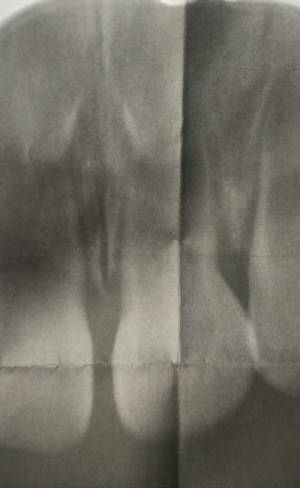

0歳児のレントゲンをどうやって撮るのか想像がつきませんでしたが、まるで非接触型の体温計のような機械を使って診察台の上で撮影していました。

レントゲン写真を見たところ、乳歯の真上にすでに永久歯が生成されていることに驚きました。

幸い、現地点で生えていた8本の乳歯と、前方の歯茎の中に生成されている永久歯、いずれも問題はないとのことでようやくホッと胸をなでおろしました。